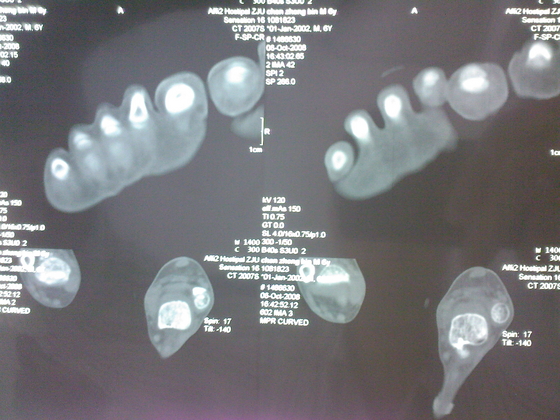

把病理送浙一医会诊后诊断为:骨外软骨瘤。同时做了CT检查。暂未予治疗。

今天把创面情况跟CT发上请大家看看。

继续发CT片

继续还有几张。